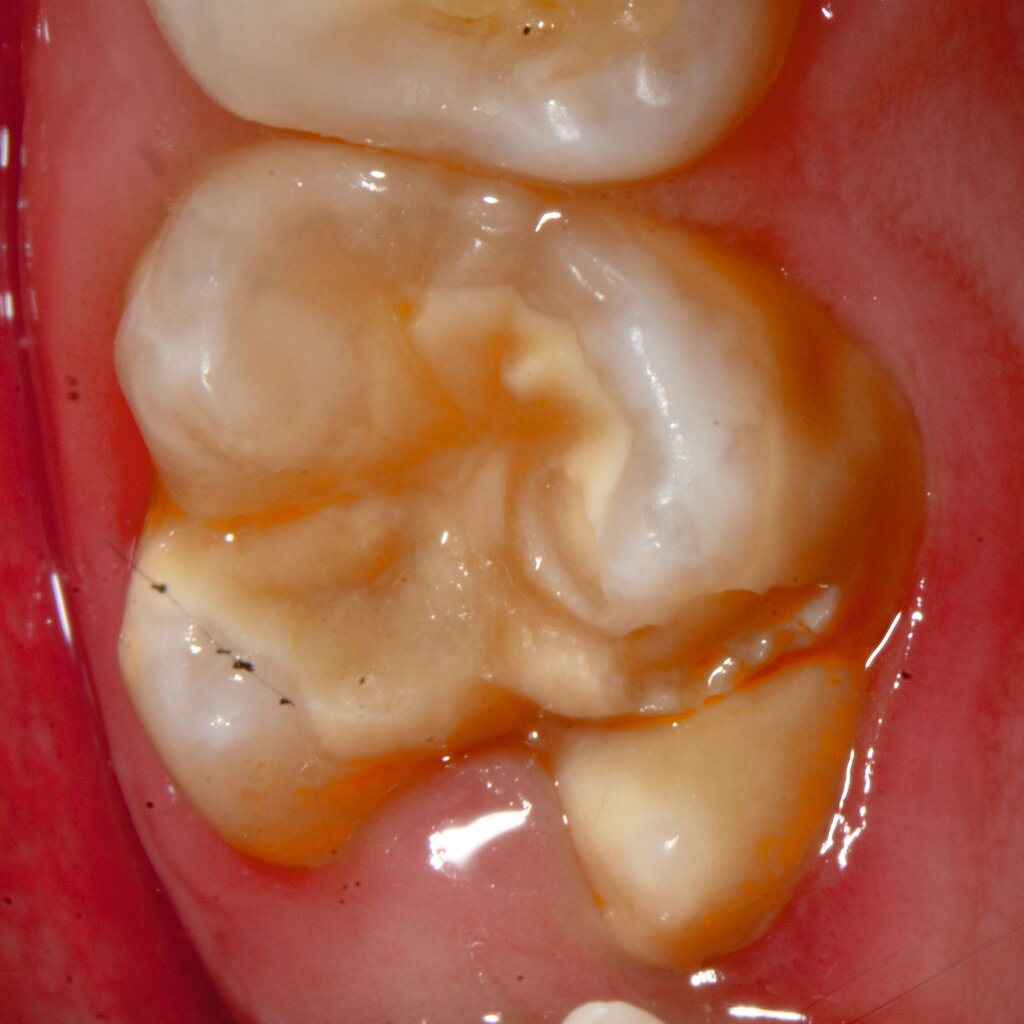

An umfangreich hypomineralisierten Zähnen können Schmelzeinbrüche (engl.: „enamel breakdown“ oder „enamel desintegration“, Abbildung 5) auftreten [Lygidakis et al., 2010; 2022]. Da diese oftmals die Folge einer fehlenden Belastungsfähigkeit des Zahnschmelzes sind und erst nach der Einstellung der Zähne in die Okklusion auftreten, werden sie auch als posteruptive Schmelzeinbrüche bezeichnet. Sie sind häufig im Bereich der Kauflächen beziehungsweise Höcker der Molaren zu finden, führen zur Dentinexposition und damit einhergehend zu ausgeprägten Hypersensitiven insbesondere bei Kindern, deren Zähne gerade erst durchgebrochen sind [Linner et al., 2021].

Bei post- beziehungsweise präeruptiven Oberflächendefekten ergibt sich in einigen Fällen die Indikation zur Restauration dieser MIH-Zähne. Unter Verweis auf die Lokalisation von MIH-bedingten Hypomineralisationen außerhalb der typischen Kariesprädilektionsstellen – zum Beispiel okklusale Fissuren und Grübchen oder Approximalflächen – werden diese als „atypische Restaurationen“ (engl.: „atypical restoration“, Abbildung 6) klassifiziert. Als ein weiteres Erkennungsmerkmal gilt die Präsenz von Hypomineralisationen im Bereich der Restaurationsränder. MIH- und kariesbedingte Restaurationen können und sollten sicher voneinander abgegrenzt werden.

Für die Dokumentation und Klassifikation der MIH wurden verschiedene Systeme vorgeschlagen. Als historisch und veraltet gilt der (modifizierte) DDE-Index. Demgegenüber haben die Kriterien der EAPD – abgegrenzte Opazitäten (Abbildung 3 und 4), Schmelzeinbrüche (Abbildung 5), atypische Restaurationen (Abbildung 6) – mittlerweile die weiteste Verbreitung gefunden. Diese wurden 2003 erstmals zur Beschreibung der MIH auf empirischer Basis publiziert [Weerheijm et al., 2003] und den Jahren 2010 und 2022 im Rahmen der damaligen MIH-Workshops bestätigt [Lygidakis et al., 2010; 2022].